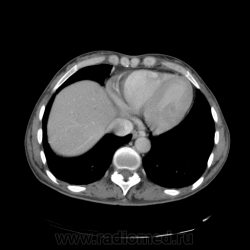

КТ ОБП - гепатомегалия, признаки панкреатита

МРТ ОБП - от 16.12.10 гепатомегалия, расширение панкреатических протоков.